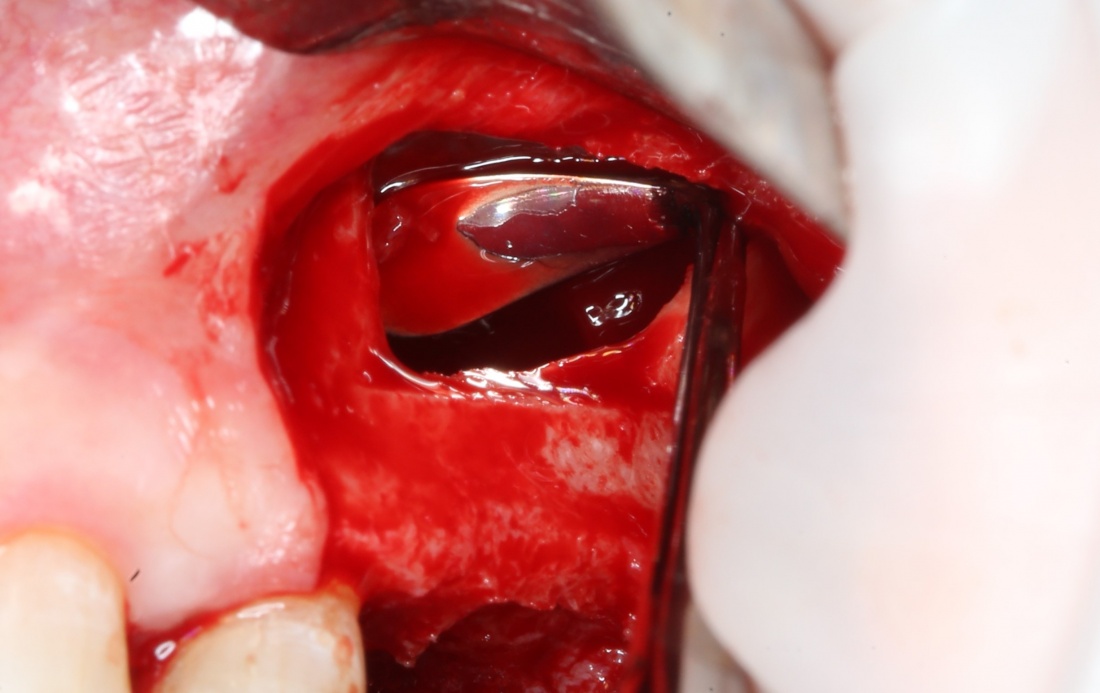

Кстати, обрати внимание на ширину альвеолярного гребня (левая картинка). Она чуть меньше 3 мм. Это объясняет, почему я засомневался в возможности установки имплантатов одновременно с остеопластикой. Понятно и без КЛКТ.

Возвращаемся к основной операционной области. Еще раз посмотрим на альвеолярный гребень, поофигеваем от его ширины и моих грандиозных планов: